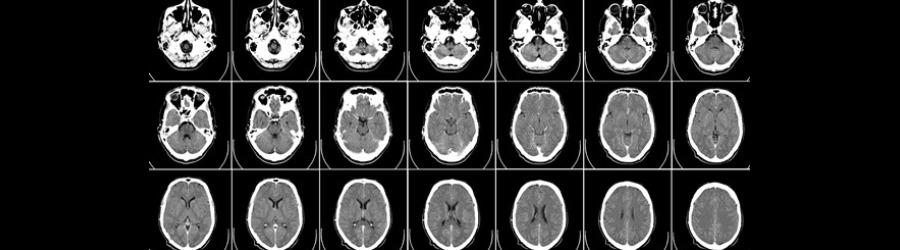

Research in Psychology and Neuroscience progresses rapidly; we discover more about how we learn and how our memories work. This online course will provide a guided tour through the brain, looking at the changes that occur on a cellular level when we learn new information or store a memory. We will examine the way the brain changes from child to teenager to adult, and how these affect the way we learn and remember information. By understanding more about the way memories are stored and recalled, we can explore different ways to help improve this process, at any stage of our lives.

Purpose: To introduce students to the neuroscience of learning and memory, and our limitations in its understanding. We will cover the reconstructive nature of memories, false memories, and their implications. By studying this week the students should have:

- Know the main brain regions implicated in memory and learning.